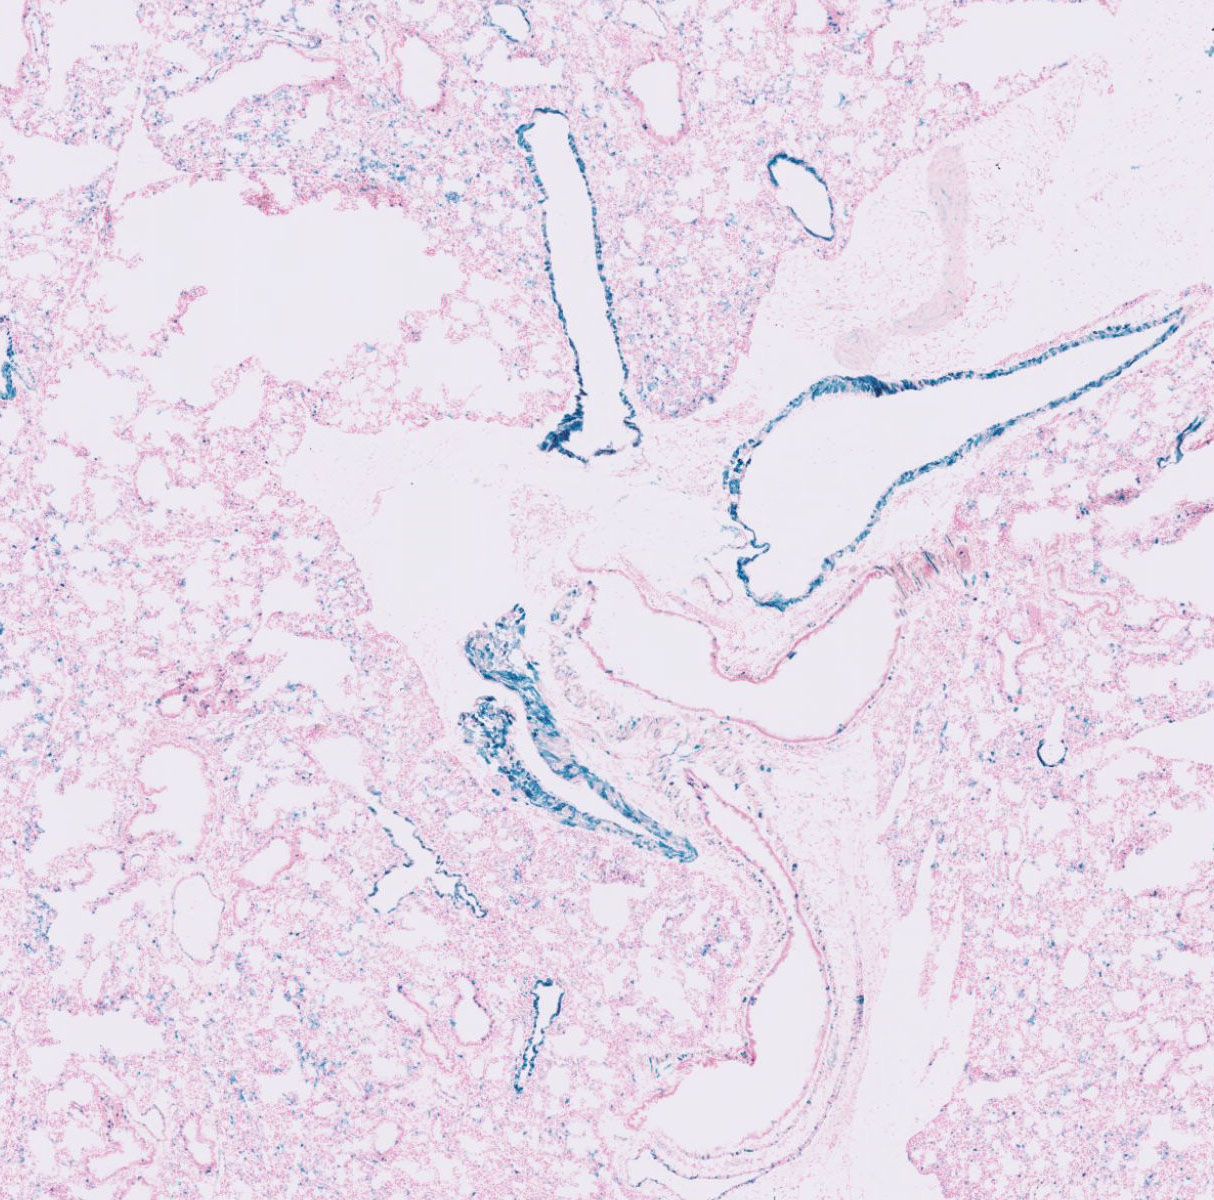

J:76130

Fig. 7